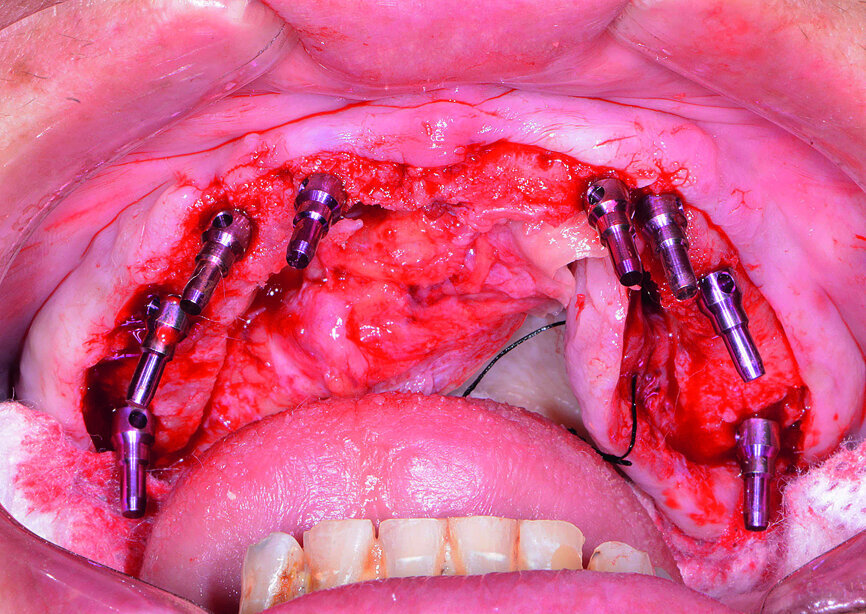

Fig. 9: Placement of maxillary surgical guide.

Fig. 10: Paralleling pins placed.

Fig. 11: Hahn dental implant being inserted.

Fig. 12: Healing caps placed.

At the surgical appointment, intravenous sedation was administered to the patient. The bone-level surgical guide was seated over the patient’s maxilla once the tissue had been reflected, and the fixation pins were tightened (Fig. 9). The implant osteotomies were created following the simplified surgical protocol of the Hahn Tapered Implant System. Eight implants were placed from second molar to second molar in the maxillary arch (Figs. 10 & 11). Healing abutments were connected to the implants to help prepare the soft tissue for the restorative phase (Fig. 12).